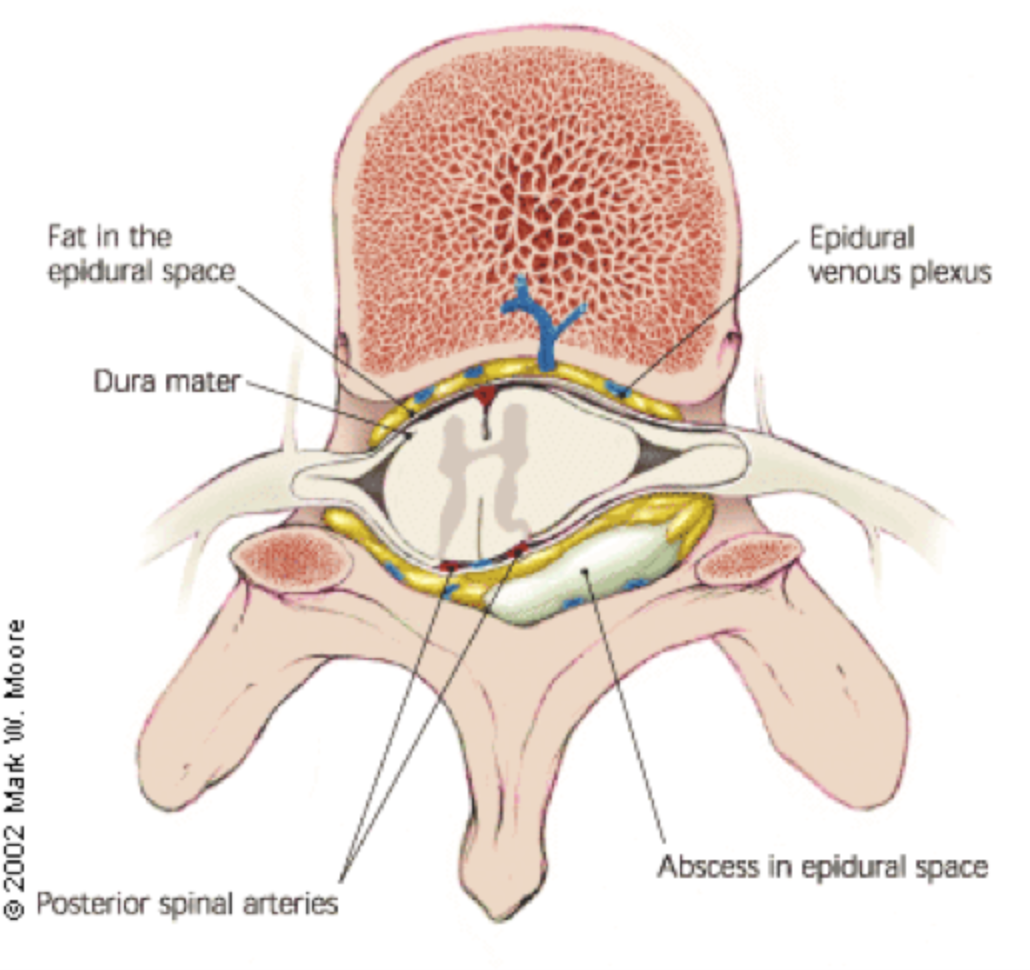

It’s usually caused by an infection and produces pus Phlegmon is an area of soft tissue or fluid density effacing or displacing usual fat or other connective tissue and shows variable enhancement However, an abscess typically has a. A phlegmon is a localized area of acute inflammation of the soft tissues

A phlegmon results when an acute infection is not confined as in the case of abscess

Instead the infection spreads along tissue planes and between muscle fibers. Phlegmon is a serious skin infection that affects the soft tissues, leading to inflammation and a collection of pus It is often caused by bacteria entering the skin through a. This article explores the causes, symptoms, diagnosis, and treatment of phlegmon, including its classifications based on clinical course, severity, location, cause, pathogenesis,.

Phlegmon is an unpleasant infectious disease manifested by inflammatory deposits, especially on the skin of a person What is the cause of phlegmon, its first symptoms and. Phlegmon is a type of deep tissue infection that can occur in various parts of the body It can manifest in different forms depending on the location and underlying cause